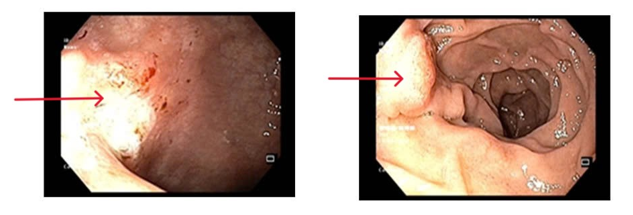

- Nội soi dạ dày: Niêm mạc hang vị phù nề xung huyết, rải rác có vài trợt nông và có hình ảnh viêm teo niêm mạc dạ dày (C2), bờ teo lan qua góc bờ cong nhỏ. Mặt trước hang vị có ổ loét kích thước ~ 0.8cm, bờ phù nề, đáy phủ giả mạc trắng

Hình 1: Hình ảnh nội soi dạ dày có tổn thương phù nề xung huyết tại niêm mạc hang vị (bên trái) và ổ loét ở mặt trước hang vị (bên phải)

- Nội soi đại tràng: Đoạn cuối hồi tràng niêm mạc mềm mại, không có loét. Manh tràng có sùi loét lớn, bờ thâm nhiễm cứng (sinh thiết). Đại tràng: Đại tràng chuẩn bị chưa sạch, còn dịch phân hạn chế quan sát. Phần quan sát được: Niêm mạc hồng, nhẵn, không có u, không có loét. Trực tràng: Niêm mạc hồng, nhẵn, không có u, không có loét.

Hình 2: Hình ảnh nội soi đại tràng có tổn thương sùi loét lớn bờ thâm nhiễm cứng tại manh tràng (bên trái) và hình ảnh niêm mạc mềm mại tại hồi tràng (bên phải)